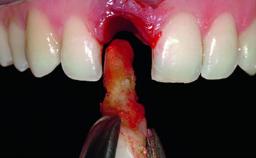

A healthy 37-year-old female patient was referred for a consultation on the replacement of missing tooth 21 with an implant-supported restoration. She stated that several years previously the tooth had been traumatically avulsed following a motor vehicle accident. The tooth was replaced with a three-unit fixed partial denture (FPD) immediately afterwards. Over time, she became disillusioned with the FPD and looked for a different option, including orthodontic therapy. She presented still in her orthodontic appliances, with the pontic sectioned free from the FPD but attached to the archwire. Her orthodontist felt that orthodontic treatment had been successfully completed, but nevertheless referred her before removing the appliances in case adjustments were necessary.

| Bone Augmentation | Horizontal|Simultaneous |

| Soft Tissue Grafting | Simultaneous |